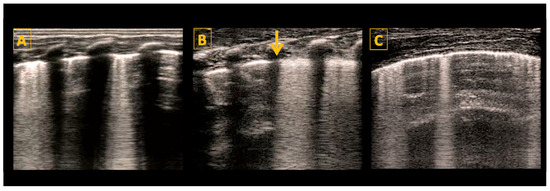

5.4. Lung Ultrasound Features and Signs

5.4.1. A-Lines

5.4.2. B-Lines